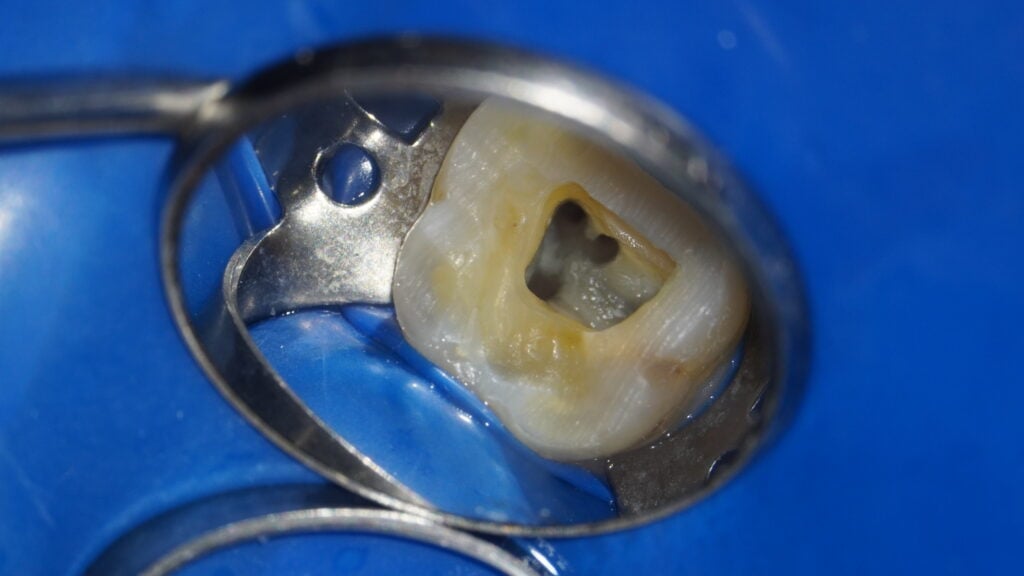

無菌環境を維持する

ラバーダム防湿とは、治療する歯以外を医療用のゴムシートで覆い、唾液や呼気に含まれる細菌の侵入を防ぐ治療法です。根管治療は無菌的な環境が大前提であり、細菌をいかに排除するかが成功のカギです。

当院では保険診療、自費診療を問わず、全ての根管治療にラバーダム防湿を徹底し、治療中の再感染を防止しています。